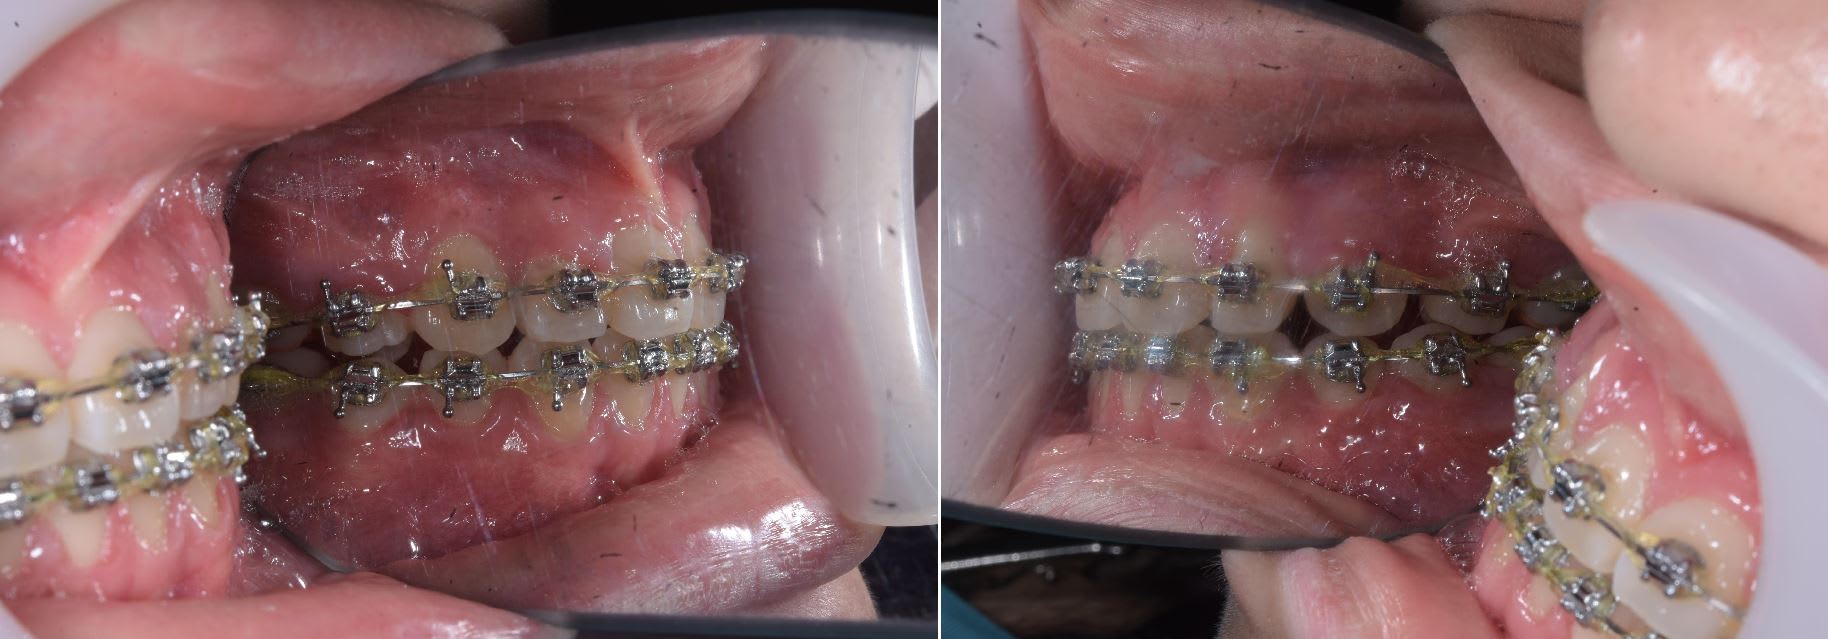

Patiente ayant commencé son traitement en Nouvelle Zélande, le dentiste lui ayant dit qu'elle en avait pour un ou deux mois grand max pour finir.

Discussion un peut tendue avec la maman pour expliqué que non en un mois ça allait pas être possible, qu'il fallait plutôt un ans et extraire une incisive du bas ( car en cas d'agénésie la substitution c'est un peut la meilleur solution )

La patiente à était une championne avec les élastique et 5 mois plus tard ( ou aujourd'hui ) ont à put enlever les bagues.

C'est pas parfait mais c'est mieux que de continuer en Suisse ( car la maman à déjà payé pour le traitement en NZ, au Cambodge et trouve qu'il n'y a pas matiére à continuer les dépenses en Europe ).

On va lui donner demains des aligneurs plastique pour améliorer l''alignement et le traitement sera fini à son retour dans deux ans.

Les photos ont était prise à larache car je voulais montré le cas à un dentiste de mon hosto pour qui c'est " sacrilége que d'extraire une incisive" .

Normalement je prend les photo le lendemain ( ce que je ferais d'ailleurs ). Y a pas que le miroir qui pose soucie, le flash n'était régler que pour éclairer un seul coté, d'ou l'ombre moche du coté gauche.

la substitution est une bonne alternative afin de terminer en classe 1 canine et molaire droite et gauche et assurer par conséquence la stabilité à long terme .

on dirait que la 33 a pris la place de la 32 !

la 23.24.33 doivent être tipper et c' est bon .